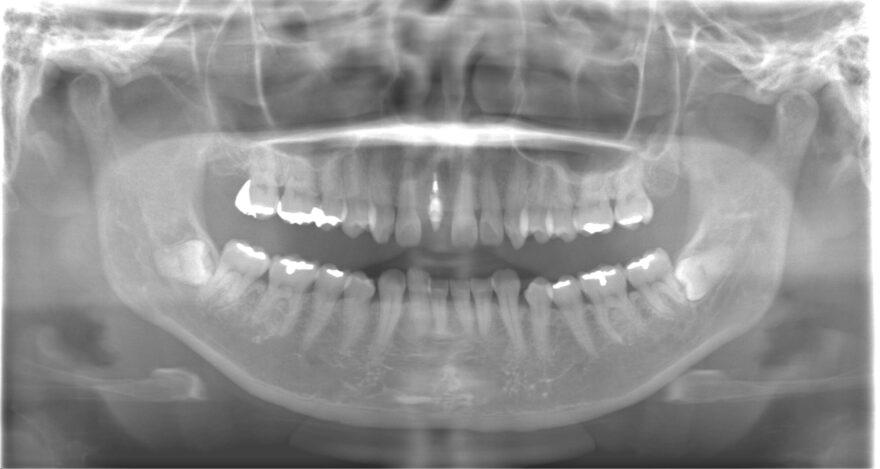

初診時のレントゲン写真